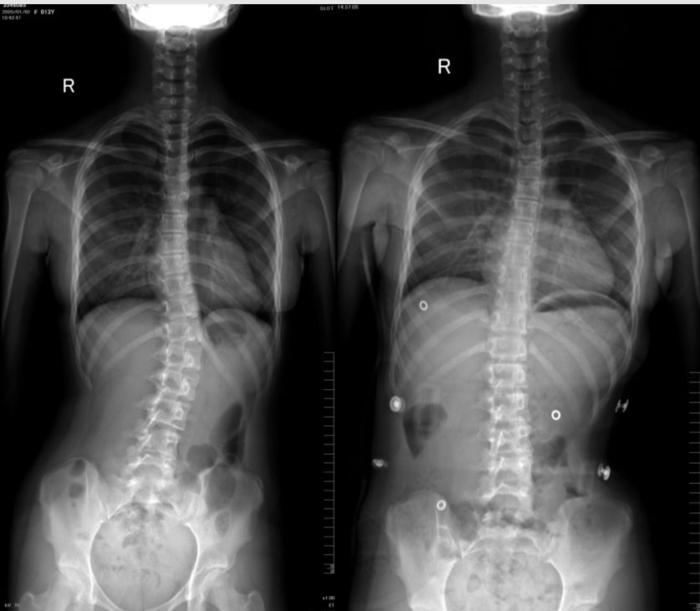

初诊:2020年1月,患者女13岁,例假一年有余,一年前发现脊柱侧弯约17°,未予以及时的重视,经过一年发展,再检查已加重至25度。经医生建议佩戴矫形器,在外地支具室看过部分矫形器后感觉比较笨重,外观相对较差,孩子比较抗拒,经网上了解到3D打印技术,遂至我院3D打印中心门诊就诊。

临床检查:患者risser征3级,体表剃刀背明显,scoliometer测量旋转约15度。

患者穿戴支具后拍片,效果明显。侧弯角度明显降低,且无明显不适感,旋转度和力线均有好转。